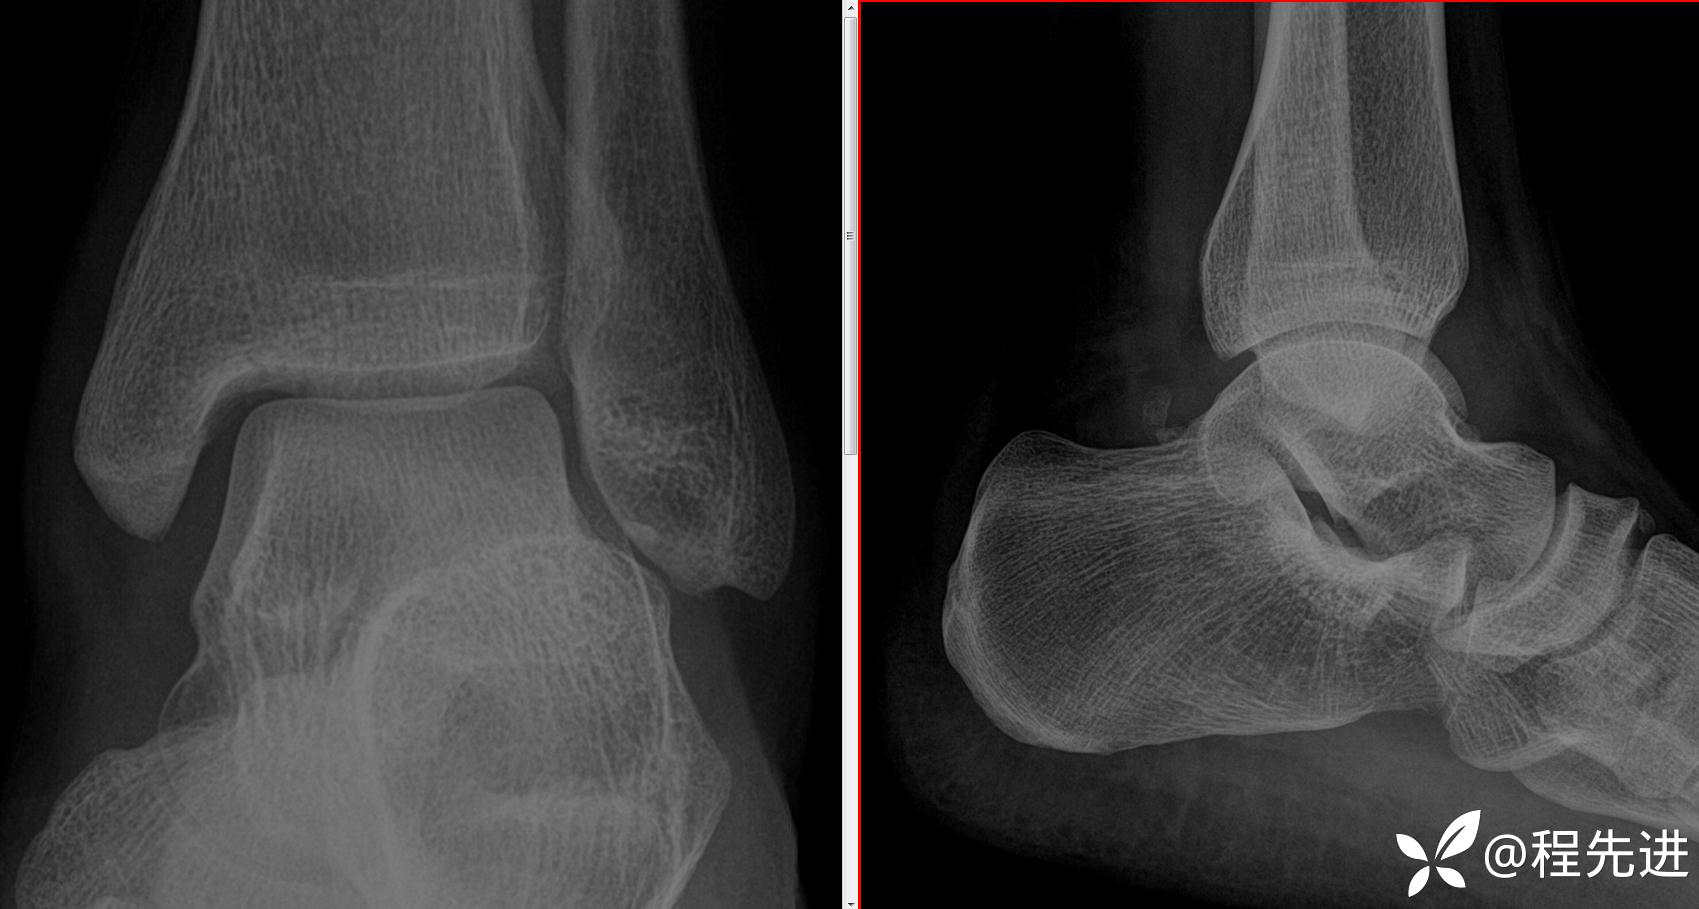

病例8月特别精彩病例|车祸致左踝关节疼痛半小时,CT证实有骨折|结果已公布

患者性别:男

患者年龄:30岁

简要病史:车祸致左踝关节疼痛半小时

辅助检查:CT检查示左踝关节骨折

来张特写,睁大眼睛仔细瞧